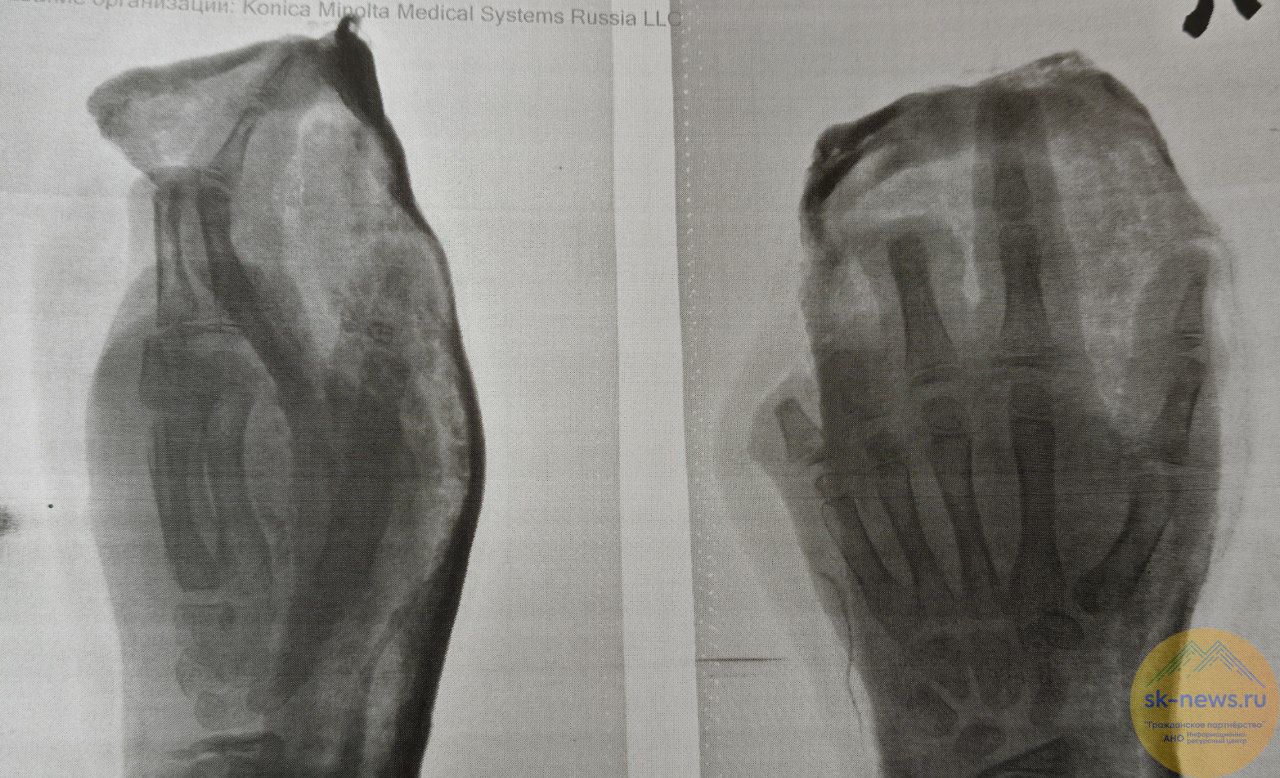

Во Владикавказе снова лечат детей, тяжело пострадавших от взрыва пиротехники. Двое мальчишек нашли на улице петарду, и при попытке ее поджечь она взорвалась прямо в руке у одного из них.

Оба ребенка получили минно-взрывные травмы, сообщили